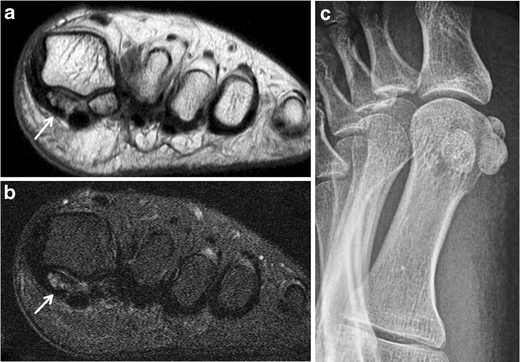

Bony sesamoiditis in a patient with plantar forefoot pain. Short axis PD (a) and T2-weighted fat-saturated (b) images reveal a mild asymmetric pattern of bone marrow oedema confined to the medial hallucal sesamoid. Note lack of oedema in the lateral hallucal sesamoid, first metatarsal head and surrounding soft tissues. Oblique sesamoid radiograph (c) shows no discernible abnormality. These results suggest bony sesamoiditis or stress reaction